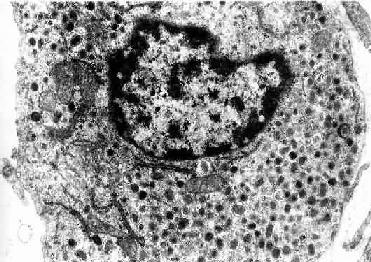

肾上腺皮质细胞分泌的激素均属类固醇,都具有分泌类固醇激素细胞的超微结构特点。如肾上腺皮质细胞。特别是束状带细胞胞质内含有丰富的滑面内质网和脂滴,线粒体嵴多呈小管状或小泡状(图11-6)。

图11-6 猴肾上腺皮质束状带细胞电镜像 ×14600

L脂滴,M线粒体

(白求恩医科大学尹昕、朱秀雄教授供图)